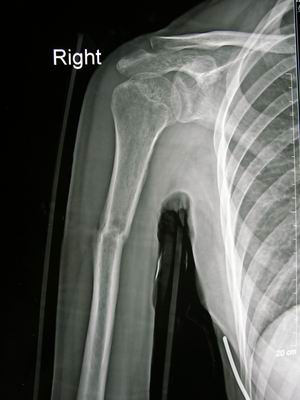

用几张系列的图片(X光片)来展示,可以更形象的看出来。

肱骨干骨折